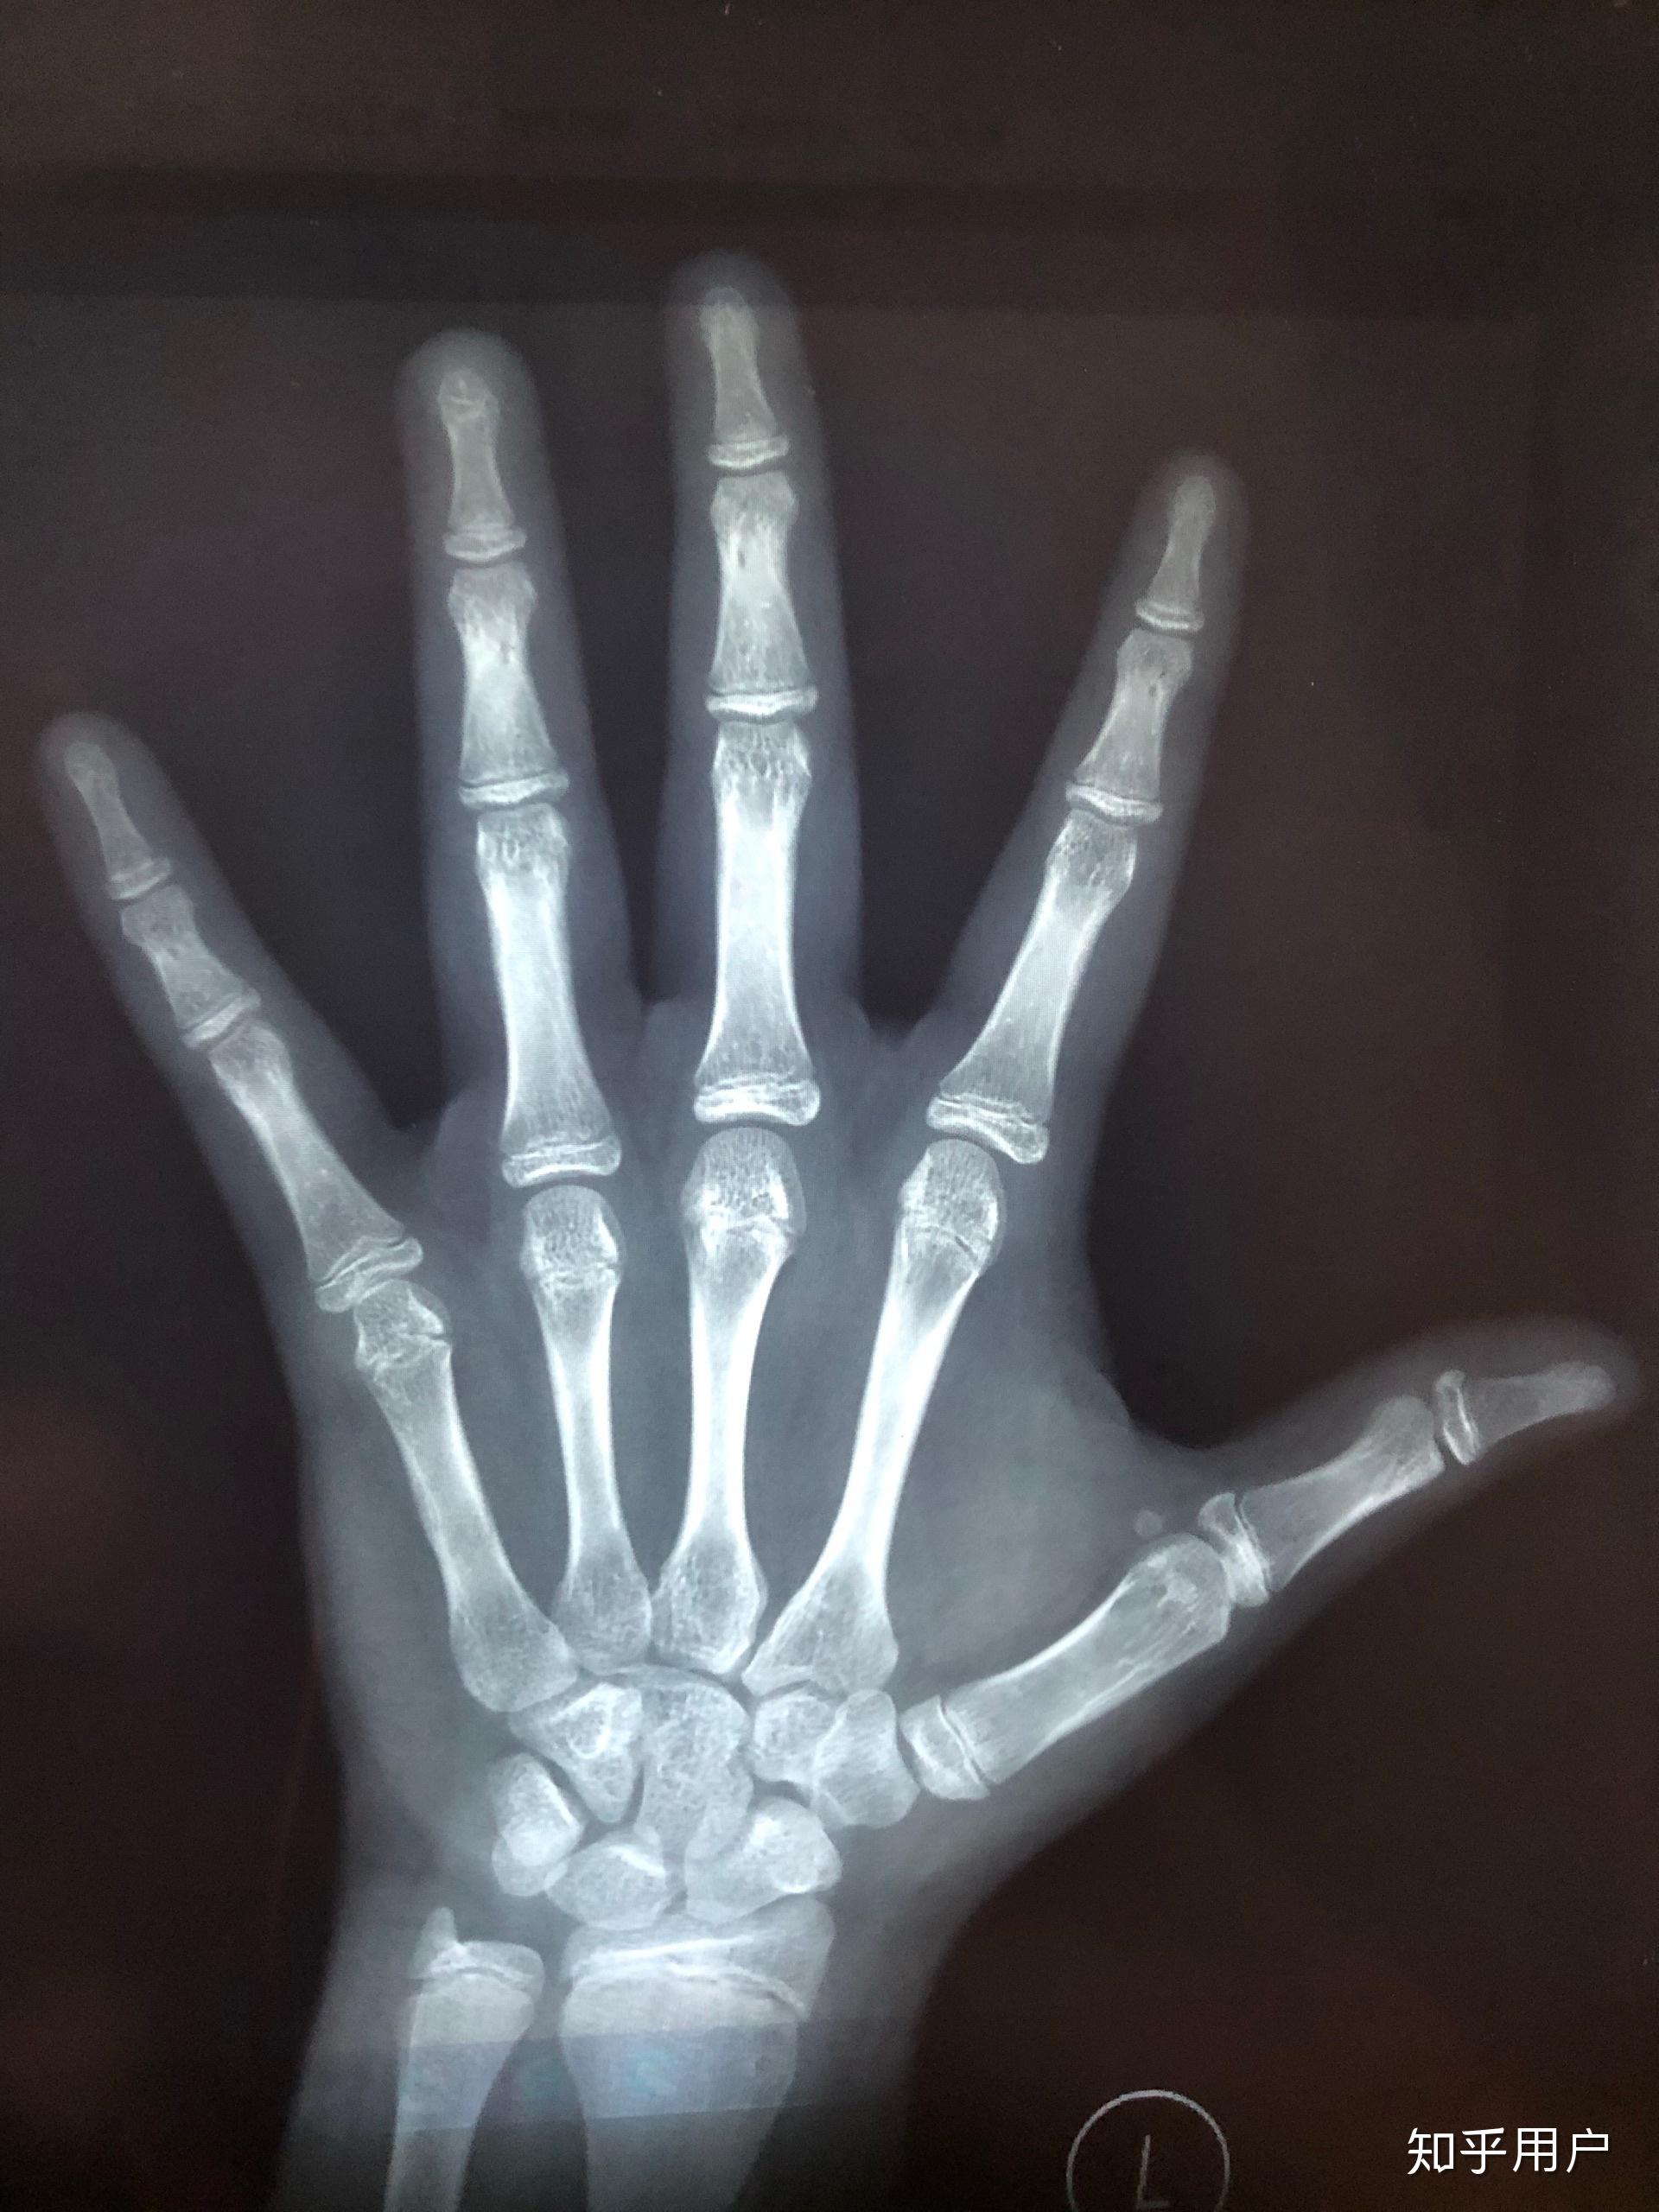

5、查骨骼闭合需要挂骨科,骨骼闭合主要通过影像学检查来确定如果是儿童,还需要有经验的儿科医生或者儿骨科医生进行检查到医院进行X光的检查,有时可以通过手部的X线检查膝关节的X线检查或者足部的X线检查来确定骨龄如果骨骼完全闭合,X光显示没有骨骺线,此时就能确定骨骼完全闭合如果存在骨骺线,肢体。

8、要确定骨骼线是否闭合以及是否还能长高,您应当前往医院的内分泌科或儿童生长发育科进行咨询和检查医生会通过拍摄您左手的腕关节正位X线光片来评估您的骨龄和骨骺线状态这种检查可以帮助医生判断您的生长潜力以及是否还有长高的可能性左手正位片是一种常用的方法来评估骨龄,因为它能够提供手腕掌指骨。

10、检查骨骼是否闭合应挂骨科科室选择在正规医院中,骨科是负责骨骼系统相关疾病的诊断和治疗的主要科室因此,要检查骨骼是否已经完全闭合,应前往骨科就诊检查方法骨科医生会通常要求拍摄关节部位的普通X线正位侧位片,以明确骨骺线是否已经闭合这是判断骨骼是否闭合的主要依据检查结果解读如果X线片显示骨骺线已经完全。